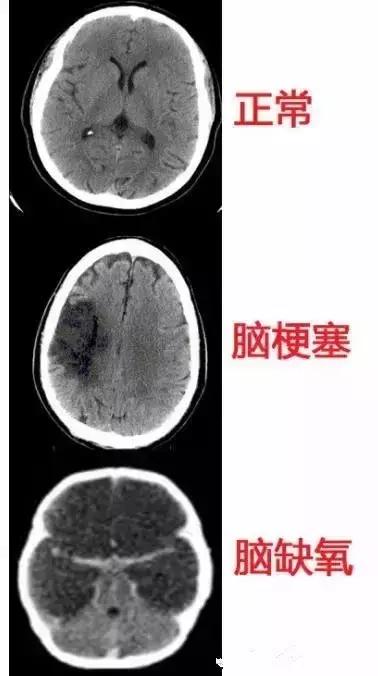

几种常见致死性脑病的CT表现

几种类型脑出血的CT表现